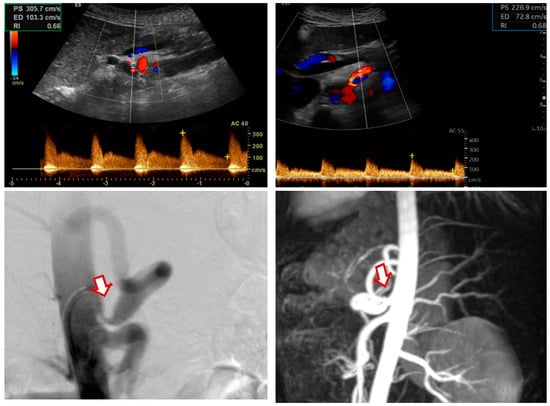

| CA PSV (m/s) in expiratory apnea, median, (Q1, Q3) | 1.5 (Q1; 1.0–Q3; 1.8) | 3.05 (Q1; 2.1–Q3; 3.3) |

| CA PSV (m/s) in inspiratory apnea, median, (Q1, Q3) | 1.2 (Q1; 1.0–Q3; 1.6) | 1.65 (Q1; 1.6–Q3; 2.5) |

| CA EDV (m/s) in expiratory apnea, median, (Q1, Q3) | 0.35 (Q1; 0.3–Q3; 0.6) | 0.95 (Q1; 0.5–Q3; 1.4) |

| CA EDV (m/s) in inspiratory apnea, median, (Q1, Q3) | 0.35 (Q1; 0.3–Q3; 0.5) | 0.85 (Q1; 0.6–Q3; 1.4) |

| Difference PSV (m/s) expiratory–inspiratory, median | 0.3 | 1.4 |